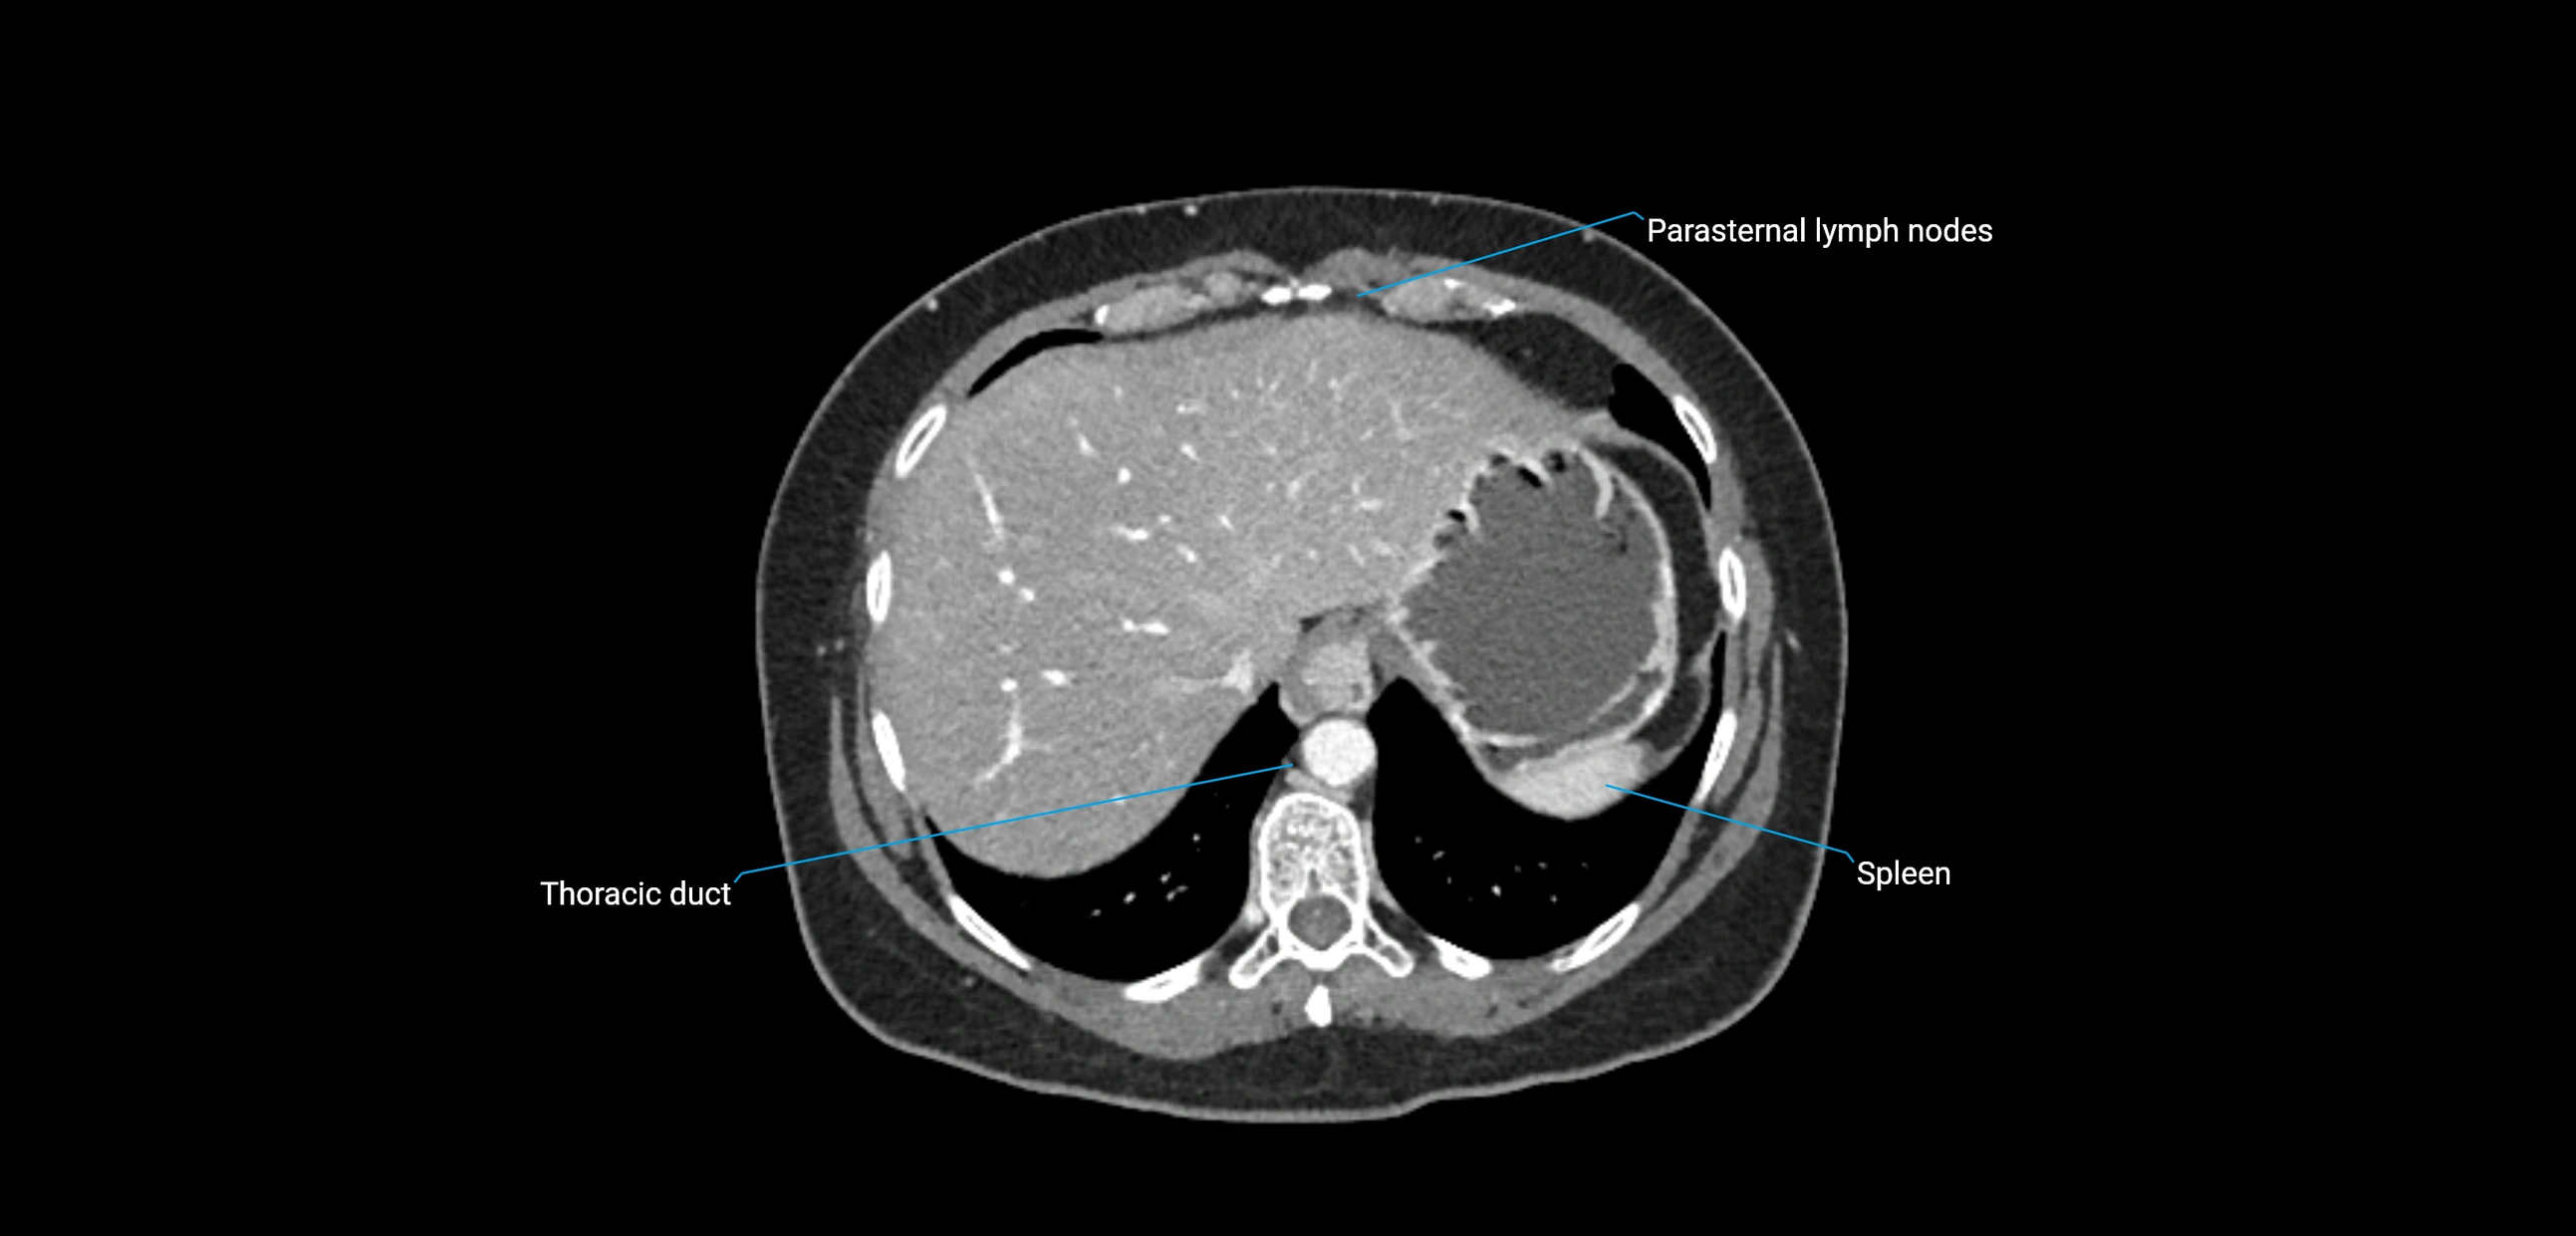

CT Appearance

CT Post-Contrast:

• Normal nodes enhance homogeneously

• Malignant nodes may show heterogeneous enhancement, central necrosis, or conglomerate formation

• Size >1 cm short axis is suspicious, though morphology and distribution are equally important

CT Venography (CTV):

• Demonstrates nodal encasement or compression of adjacent vessels (aorta, IVC, renal veins)

• Useful in staging testicular and ovarian malignancies

• Provides 3D reconstructions for retroperitoneal lymph node dissection planning